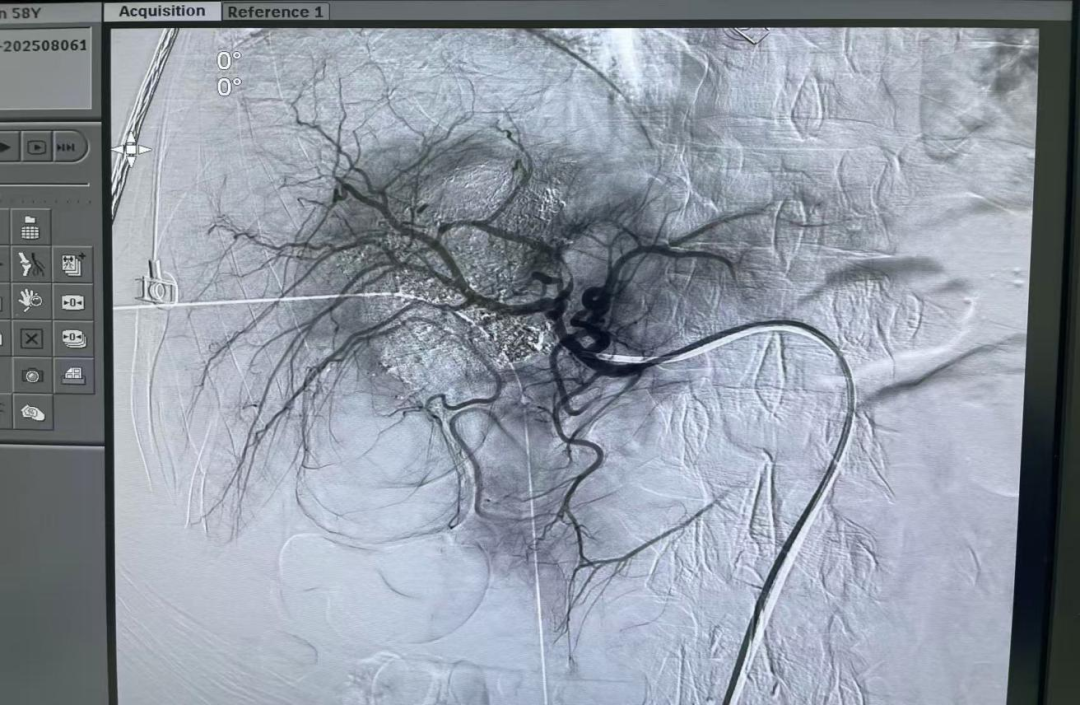

圖4:患者股動(dòng)脈予以血管鞘及導(dǎo)管外固定。